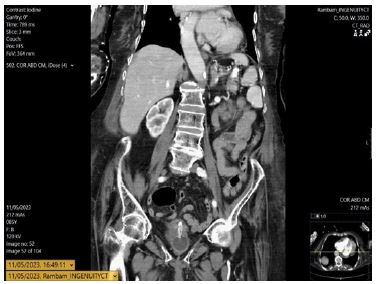

In 2023, 11 years post-insertion, she presented with suspected internal PEG migration. The external stoma was clean, but the tube was absent. Abdominal CT located the tube in the duodenum.

A temporary Foley catheter secured the tract. Subsequent endoscopy did not visualize the tube in the duodenum but found the gastrostomy device within the stomach (Figure 1). A new 14F replacement tube was inserted. The duodenal component seen on CT was presumed likely to pass spontaneously (Figure 2), and the patient was monitored for obstruction.

Figure 2: Coronal view of the patients abdominal computed tomography showing what seems is the gastrostomy tube.